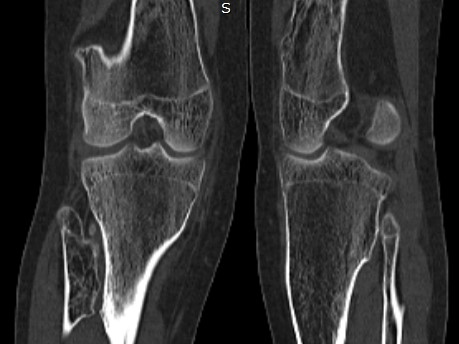

A 12-year-old girl reported pain in the lower limbs, wrists and knees 3 years ago. She evolved with leg pain when walking, edema and asymmetry of the legs and in the circumference of the knees. One year ago, a punctiform bone protuberance appeared near the right external malleolus. A maternal aunt was diagnosed with multiple osteochondromatosis. Physical examination: overall decrease in skeletal muscle strength, antalgic posture, swollen knees, painful limitation of knee movements, abdormal gait and fixed posture in valgus knees. Referred to Rheumatology due to suspicion of Juvenile Idiopathic Arthritis because she had deformities in the knees and pain in different joints; however, it was observed that there was no associated arthritis. Laboratory tests without alterations and computed tomography (CT) revealed the presence of multiple osteochondromas (Figure 1-3), indicating a bone metaplasia, compatible with the diagnosis of multiple osteochondromatosis.1,2

Figure 3 Coronal view of CT showing a osteochondroma in the distal segment of the left tíbia (White arrow) and left fíbula (blue arrows).